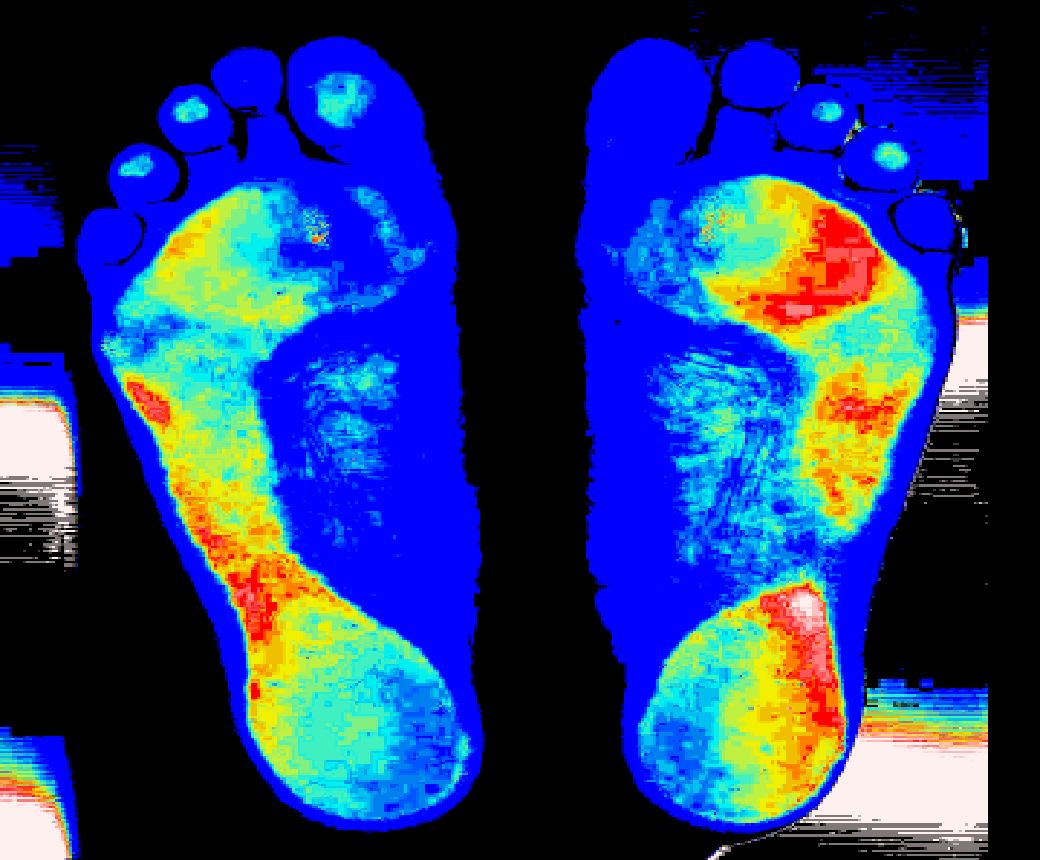

Before

身体に問題を抱えてる人は足の一部分でしか支えていません。

After

コロコロさんを転がす事で足全体で支える事ができます。

(足底圧画像)